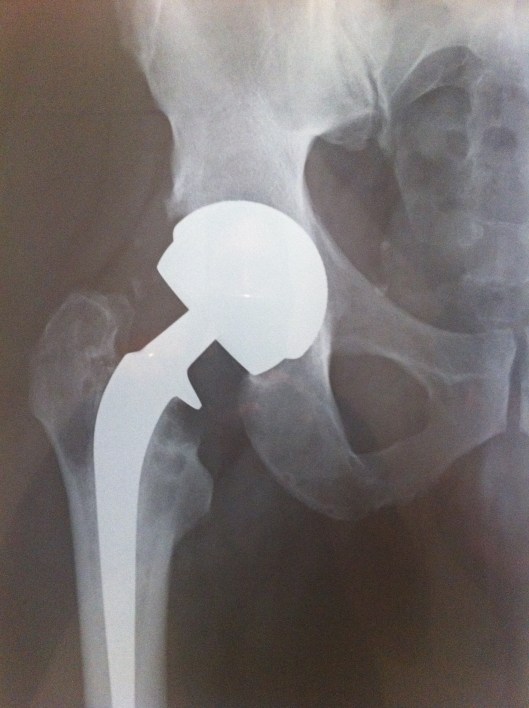

X-rays were taken in the Gold Coast Hospital Outpatients Clinic while I waited – great service – thanks guys!

The x-rays confirmed the arthritis in the left hip and this is going to need replacing.

However, it was the right hip, with the Smith & Nephew Birmingham Spectron total hip replacement which caused the most interest:

- Severe oestolysis around the hip – tissue damage.

- Bone erosion (gone totally) for several centimeters below the collar on the inside leg side.

- Damage to the bone on the outside leg side – mottled and insubstantial-looking.

- Signs of movement of the femoral stem of the hip implant – lines down either side and possible bone damage – the cement contains ceramic and this can then act as a grinding past as the stem moves. This has the potential to release more metal ions.

- These signs of movement may explain the feeling of “popping in and out” that I feel – but without dislocation of the hip prosthesis.

Had some new X-rays done today – two months since the last ones – seems to me that there is more osteolysis and bone loss – possibly some fragments but I am not a medical doc and I haven’t discussed these with the surgeon yet. Will do on the day of the surgery.

What is interesting is 3 radio-opaque spots showing up in the pelvic area – not sure what those are.

Quality of the photo’s below – OK for an iPhone 4 shot of the X-Rays held up by my son against a white background!